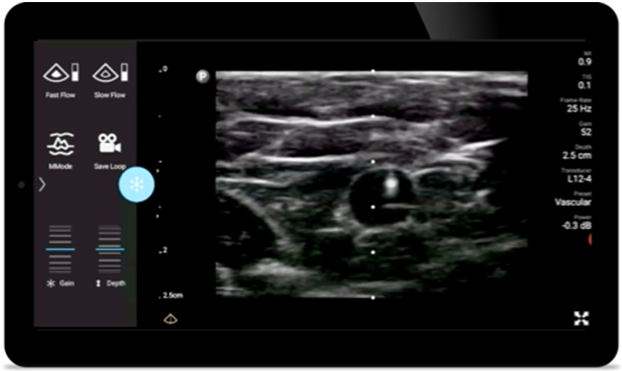

Lumify L12-4 broadband linear array transducer

• 12 to 4 MHz extended operating frequency range

• Aperture size: 34mm

• 2D, steerable color Doppler, M-mode, advancedXRES and multivariate harmonic imaging, SonoCT

• High resolution imaging for shallow applications: soft tissue, vascular, superficial, musculoskeletal and lung

• Center line marker

• USB-C transducer with replaceable cable